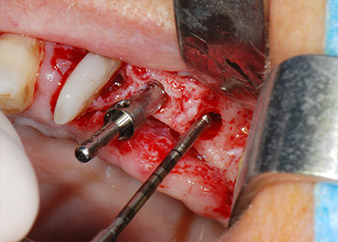

Sinuslift und Einbringen der Implantate

Vor der Insertion der Implantate wurde infiziertes Weichgewebe im Implantationsbereich und um das Abutment mit einem Instrument entfernt, das laut Hersteller primär zur Knochenbearbeitung und zum Sammeln von Knochenspänen vorgesehen ist (Piezomed, Einsatz B5) (Abb. 6 und 7).

Implantatmotor

Abb. 8: Der nächste Schritt ist die rotierende Präparation des Implantatbetts bis kurz unterhalb des Sinusbodens an Position 25, die mit einem weiterentwickelten Implantatmotor erfolgte.

Im folgenden Schritt wurde das jeweilige Implantatbett an den Positionen 25 und 26 mit rotierenden Instrumenten in einem Winkelstück mit einem Übersetzungsverhältnis von 20:1 (WS-75 L G, W&H) und einem vor Kurzem aktualisierten leistungsstarken Implantatmotor präpariert (Implantmed, W&H) (Abb. 8 und 19).

Die Abschlusspräparation am Sinus erfolgte wieder mit einem piezochirurgischen Instrument.

Vor der Insertion der Implantate und nach Überprüfung der intakten Schneiderschen Membran (Abb.9) wurde der interne Sinusboden an beiden Implantatpositionen mittels eines xenogenen Knochenersatzmaterials (Abb. 10) augmentiert.

Dann wurden die Implantate (Restore, Keystone Dental) mit dem Implantatmotor eingesetzt (Abb. 11 und 12).

Insertion des Implantats an Position 26

Abb. 11: Insertion des Implantats an Position 26 bei geringer Geschwindigkeit und einer Drehmomentbegrenzung von 35 Ncm.

Eindrehen der Abdeckschrauben

Abb. 12: Beide Implantate sind in Position und bereit für das Eindrehen der Abdeckschrauben.